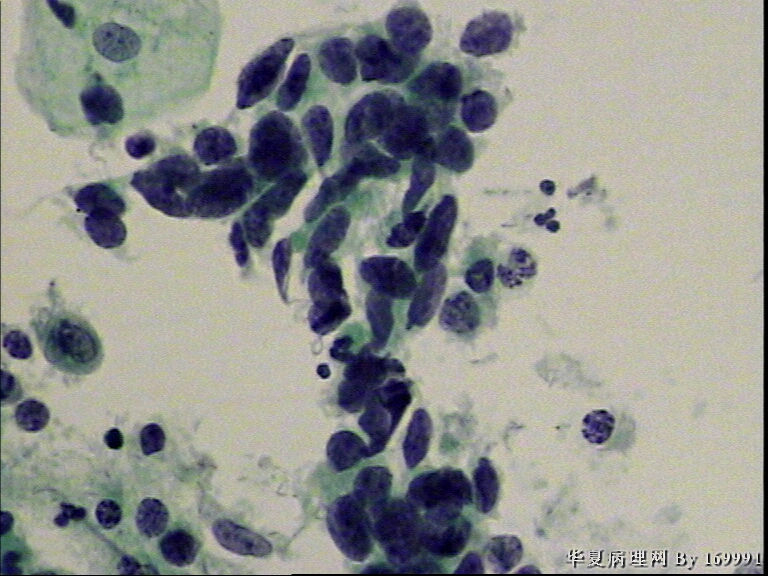

宫颈液基,患者60岁,宫颈轻糜,鳞癌?

• 宫颈液基,患者60岁,宫颈轻糜,鳞癌?图1

鳞癌

HSIL

是鳞还是腺,有待研究,建议活检与诊刮

HSIL,疑SCC,建议活检。

感觉像腺的问题较鳞的问题严重。

细胞是有问题,细胞核体积增大,核浆比增大,核的异型性也有。但是我们一般不敢打得太过,我觉得是HSIL,建议组织活检。

不是吧,今年的人气怎么也比去年强啊。腺有问题么?鳞倒是明确的。。。。。。。。。。

HSIL不排除SCC

鳞癌,建议活检。

鳞癌可能性大于腺癌,但也不能排除腺的问题,建议活检。